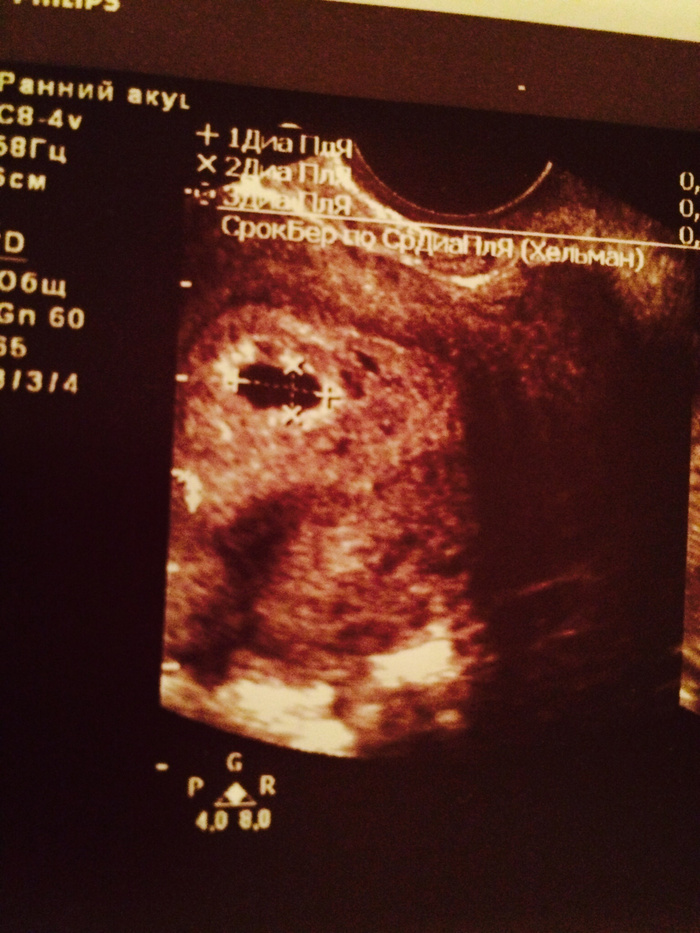

Беременность после неудачных форум 87 фото